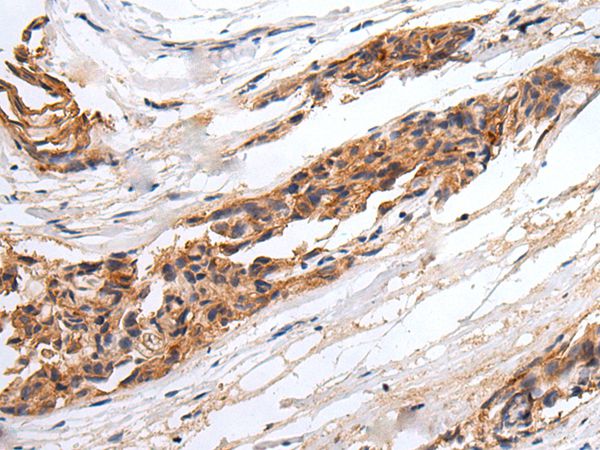

The image on the left is immunohistochemistry of paraffin-embedded Human breast cancer tissue using GABRR2 Antibody at dilution 1/25, on the right is treated with synthetic peptide. (Original magnification: x200)